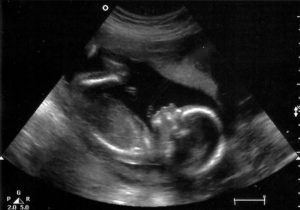

Процедура УЗИ на 19 неделе беременности проводится для выявления возможных патологий у зародыша и обследования его анатомического развития.

Данное исследование определяет и положение плода в утробе матери, что играет большую роль в том, каким способом будут проходить роды.Также с помощью аппарата врач проводит фетометрию, то есть определяет размеры окружности головы и живота, косточек рук, ног, бедер, плечиков. Просматривается симметрия внешних и внутренних органов. Определяемый пол ребенка имеет вероятность до 90%.

На основе данных, зафиксированных специалистом, делается вывод о соответствии развития плода его эмбриональном возрасту. Помимо изучения параметров развития, доктор исследует состояние матки и плаценты. При обнаружении патологий, гинеколог, опираясь на результаты, ставит диагноз и назначает лечение.

При проведении второго ультразвукового исследования подходит к концу 19 неделя беременности. Фото ребенка можно получить у врача. На снимке уже видно сформировавшегося человечка, отчетливо заметны все части тела. Современная техника позволяет сделать 3D-фото плода.

УЗИ в 19 недель позволяет убедиться в том, что малыш правильно развивается, его размеры соответствуют сроку беременности, а также дает информацию о количестве и состоянии околоплодных вод, состоянии плаценты и кровотока в сосудах, соединяющих матку, плаценту и кровеносную систему плода. Кроме того, УЗИ на этой неделе позволит узнать пол будущего ребенка .

Ребенок на 19 неделе беременности развивается быстрыми темпами. Происходят изменения в ЦНС – образуются связи между нервными клетками, увеличивается объем головного мозга. В результате происходит усложнение рефлекторных реакций, увеличивается двигательная активность плода: он часто шевелит ручками и ножками, сосет большой палец руки. Это подтверждает проводимое УЗИ.

УЗИ 19 недель беременности является вторым обязательным исследованием (всего УЗИ проводят не меньше трех раз в течение гестации).

Оно помогает определить состояние плода, особенности его развития, расположения в маточной полости, тип и место крепления плаценты.

Благодаря этому методу медикам удается диагностировать возможные нарушения, отклонения в развитии, врожденные аномалии. Кроме того, они обращают внимание и на пол младенца. Нормы основных показателей приведены в таблице.

На 19-й неделе рост плода составляет 25 см, а весит он 250—300 г.

В это время продолжается интенсивный рост ручек и ножек в длину, увеличивается в размерах туловище, а головка плода существенно замедляет свой рост. За счет этого малыш меняется внешне и уже не выглядит непропорциональным.